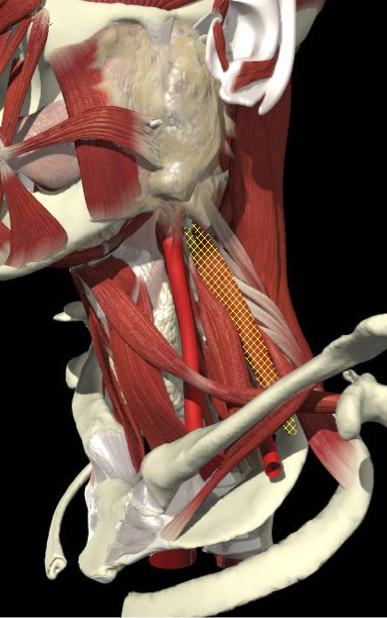

ACCURACY OF LOCALIZATION - SCALENES

ACCURACY OF LOCALIZATION LEVATOR SCAPULAE

LOCALIZATION OF MUSCLES IN DEEPER LAYERS

Layer 1

Layer 2

Layer 3

Splenius Capitis

Semispinalis Capitis

Longissimus Capitus

Semispinalis Cervicis

ACCURACY OF LOCALIZATION – DEEPER LAYERS